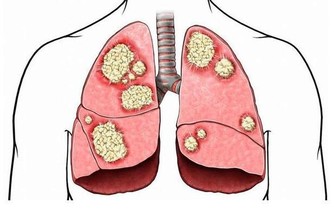

3、腸道壞菌多

腸胃中是有多種多樣細菌的,如果腸胃菌群紊亂,其中壞菌就會產生大量的氣體,也會脹氣。